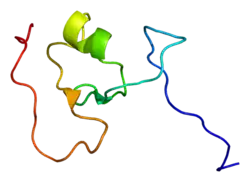

E3 ubiquitin-protein ligase TRIM63, also known as "MuRF1" (Muscle Ring-Finger Protein-1),[5] is an enzyme that in humans is encoded by the TRIM63 gene.[6][7][8]

This gene encodes a member of the RING zinc finger protein family found in striated muscle and iris. The product of this gene is localized to the Z-line and M-line lattices of myofibrils, where titin's N-terminal and C-terminal regions respectively bind to the sarcomere. In vitro binding studies have shown that this protein also binds directly to titin near the region of titin containing kinase activity. Another member of this protein family binds to microtubules. Since these family members can form heterodimers, this suggests that these proteins may serve as a link between titin kinase and microtubule-dependent signal pathways in muscle.[8]

The protein encoded by the Trim63 gene is also called MuRF1. MuRF1 is the name most commonly used in the literature, and it stands for "Muscle RING Finger 1." Structurally, there are two closely related MuRFs, MuRF2 and MuRF3. These also have TRIM codes: MuRF2 is TRIM55; MuRF3 is TRIM54.